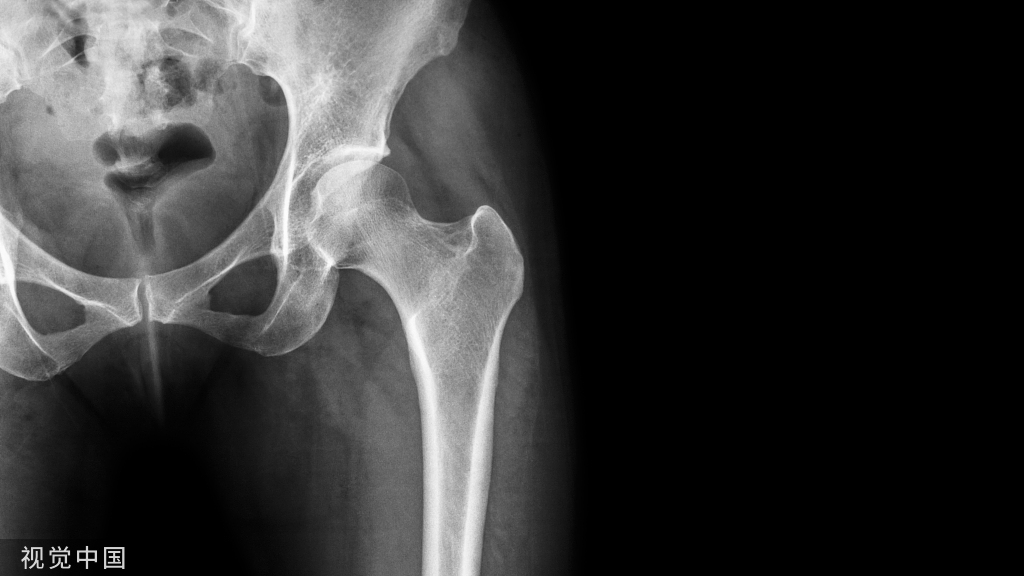

髋关节镜手术前需要做哪些检查?

根据病情不同,术前检查有所不同,力求明确诊断。如果考虑髋关节撞击综合症,要做相应的特殊体位X片(骨盆正位+Dunn位),以及单髋盂唇核磁。不建议在当地医院检查,特殊体位检查需要有经验的医生和放射科医生合作才能完成,并且磁共振和CT这些检查档次也是不同的,在当地医院的检查只能作为参考。